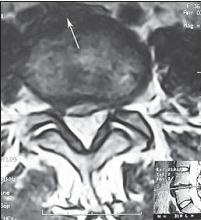

На МРТ № 18 наблюдаются грыжи межпозвонковых дисков в сегментах: — LIV-LV вентральной локализации с образованием каудального секвестра; при расположении межпозвонковой грыжи на один сегмент выше, «конфликт» с брюшной аортой был бы неизбежен; — LV-SI — дорсальная грыжа межпозвонкового диска, частично компенсированная спондилёзом МРТ № 19 ![]() МРТ № 20 ![]() На МРТ № 19 наблюдается дорсальная грыжа межпозвонкового диска шейного отдела позвоночника в сегменте СV-СVI с компрессией спинного мозга На МРТ № 20 наблюдается грыжа межпозвонкового диска шейного отдела позвоночника в сегменте CV—CVI и протрузия в сегменте CVI-CVII Замечу, что если грыжа межпозвонкового диска имеет достаточно большой размер и локализована в шейном отделе, то она способна вызвать не только соматические нарушения, но и даже психические расстройства. Причина кроется в сдавлении дурального мешка грыжей межпозвонкового диска (дуральный мешок — это герметичный соединительнотканный мешок, формируемый твёрдой мозговой оболочкой, в котором расположен спинной мозг). Как известно, спинной мозг не имеет болевых рецепторов. Однако вышеуказанная патология приводит к локальному устойчивому возбуждению определённых зон коры головного мозга. На субъективном уровне это может проявляться как постоянное чувство тревоги (так называемый «синдром ожидания»). Грыжи межпозвонковых дисков в грудном отделе позвоночника явление довольно редкое, но всё же наиболее опасное. Опасное потому, что эпидуральное пространство в грудном отделе позвоночника узкое по сравнению с другими отделами, в пределах всего 0,2–0,4 см по всей окружности дурального мешка (твёрдой оболочки спинного мозга). Поэтому даже небольшое грыжевое выпячивание может сдавить спинной мозг и вызвать тяжелейшие осложнения. Но, как уже говорилось, это явление в грудном отделе позвоночника редкое, поскольку высота межпозвонковых дисков довольно мала, всего около 3–5 мм, да и грудной отдел позвоночника менее подвижен по сравнению с другими отделами за счёт жёсткого рёберного каркаса, а значит, менее подвержен травматизации. МРТ № 21